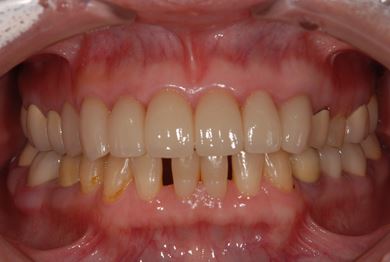

| 性別/年齢 | 女性 / 51歳 | ||||||||||||||||||||||||||||||||

| 主訴 | 前の歯の治療後の変色が気になる。詰め物がとれた箇所あり。痛みあり。 | ||||||||||||||||||||||||||||||||

| 治療方針 | セラミック治療にて、審美的回復を行う。 | ||||||||||||||||||||||||||||||||

| 治療内容 | オールセラミッククラウン7本(オールセラミック用土台1本)、ハイブリッドセラミッククラウン10本(ハイブリッドセラミック用土台9本)、ハイブリッドセラミックインレー1本 | ||||||||||||||||||||||||||||||||

| 総治療費 | 961,800円 | ||||||||||||||||||||||||||||||||

| 治療期間 | 10ヶ月 |